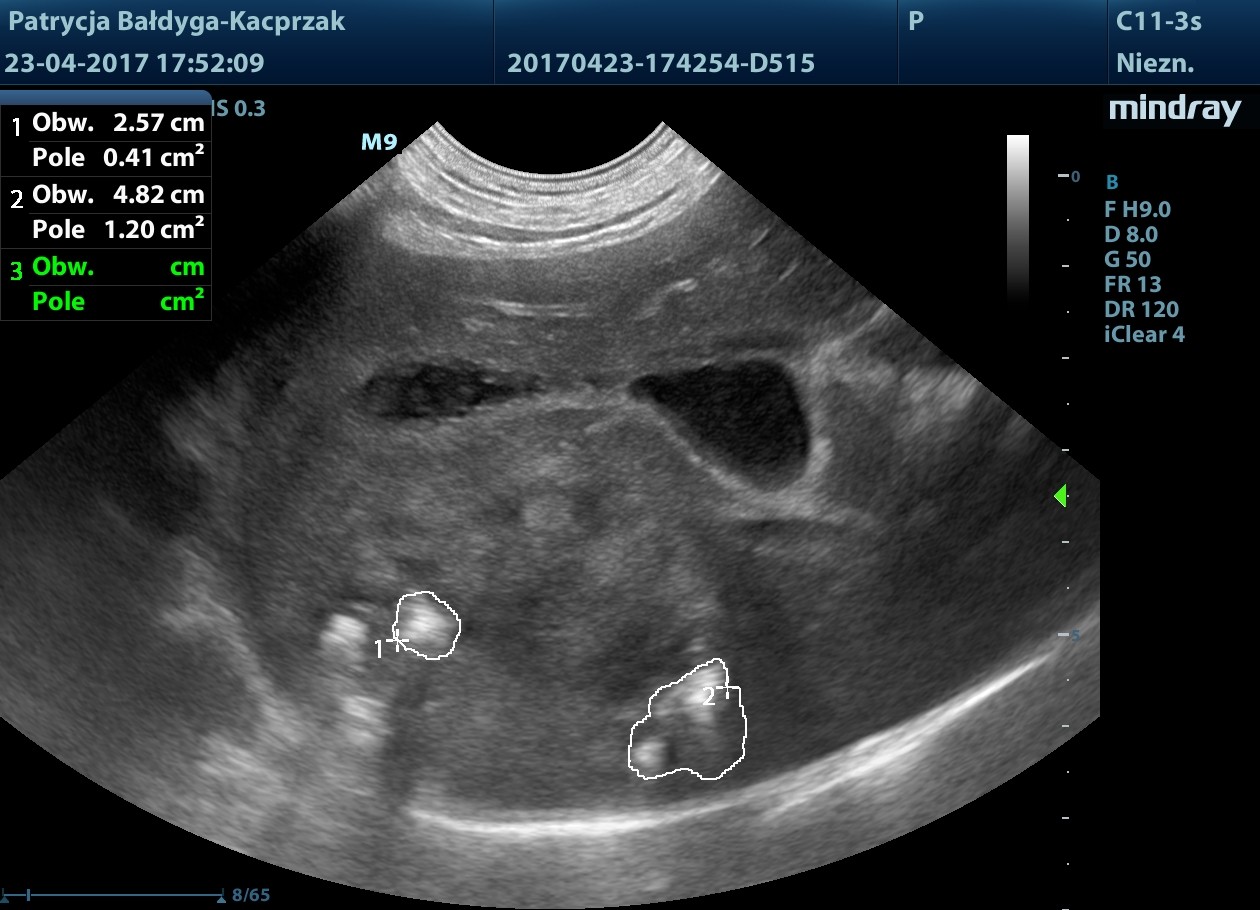

Kwiecień

Guz trzustki powiększył się

- wykonano biopsję aspiracyjną cienkoigłową.

W płatach prawych wątroby widoczne nowe ogniska hiperechogenne, okrągłe ok. 13-31 mm, podejrzenie zmian metastatycznych

pod pęcherzykiem żółciowym zmiana ok 4,5 cm z drobnymi obszarami hiperechogennymi, jak zwłóknieniowymi/mineralizacyjnymi, gazem?

obrys 1- tu lekki cień akustyczny świadczący o twardości zmiany, obrys 2- tu artefakt rewerberacji, mogący sugerować obecność pęcherzyków gazu

Wynik BAC- duże prawdopodobieństwo raka trzustki.